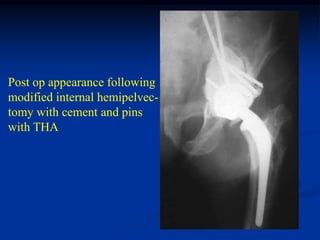

Post op appearance following

modified internal hemipelvec-

tomy with cement and pins

with THA